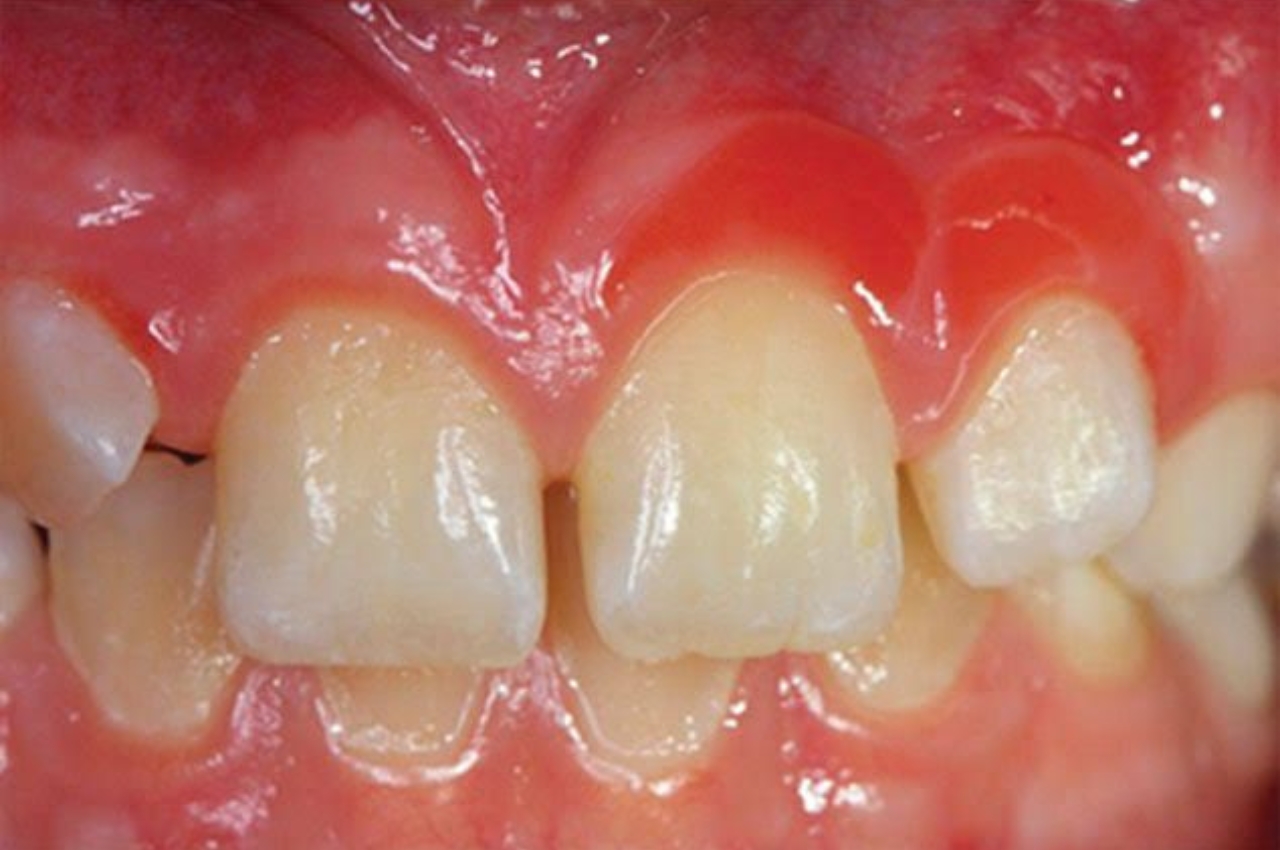

Durante su estancia, Edgar desarrolló una investigación titulada “hiperplasia espongiótica”, en conjunto con la doctora Brenda Yuliana Herrera Serna, quien fue su tutora en la UAM. El trabajo corresponde a un artículo de revisión enfocado en comprender esta lesión y analizar estrategias para su mitigación.

“La hiperplasia espongiótica es una lesión que se encuentra en pacientes sanos, que no tienen ninguna patología sistémica. Generalmente se observa cuando hay apiñamiento en pacientes con tratamiento de ortodoncia y aparecen movimientos dentales sin motivo aparente”, explicó Edgar.

Diversos estudios la relacionan con factores como:

- Mala higiene oral y acumulación de placa.

- Factores genéticos.

- Fuerzas ortodóncicas aplicadas durante el tratamiento.

Aunque en algunos casos la lesión puede remitir espontáneamente, existen situaciones en las que requiere intervención mediante remoción quirúrgica, terapia láser o aplicación de frío. La investigación desarrollada en la UAM se enfoca precisamente en analizar cómo mitigar este tipo de hiperplasia y aportar evidencia útil para la práctica clínica.